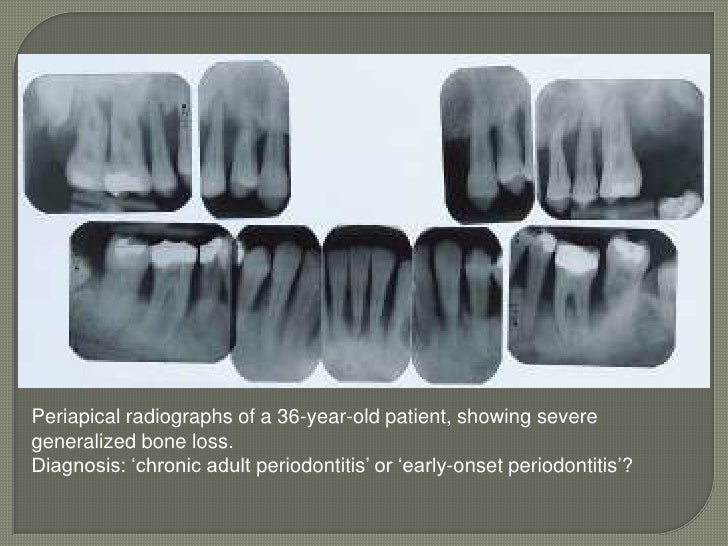

Figure 9 from Periodontal debridement still the treatment of choice Ada Code For Laser Periodontal Therapy Lapt uses the laser in the depths of the pockets to decontaminate diseased periodontal pockets. The ada code d9997 enables dental professionals to accurately code and bill for soft tissue diode laser procedures, promoting transparency in treatment records and insurance. Ada guideline offers recommendations on nonsurgical treatment of chronic periodontitis by means of scaling and root planning with or without.. Ada Code For Laser Periodontal Therapy.